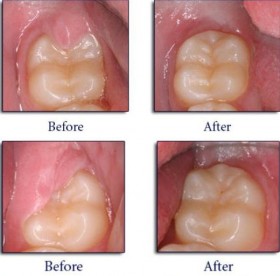

Most infants have healthy teeth at this age. However, this is the right time to analyse the growth, development and other inherited aspects of mouth and teeth. Counselling for the parents regarding oral health and hygiene forms an important part of the first visit! The most important first treatment is the tooth brushing techniques and advice for the same. A professional cleaning is recommended to ensure that your child’s mouth is plaque and bacteria free. Other treatments include FISSURE SEALANTS, FLUORIDE TREATMENTS, RESTORATIONS, PULP THERAPY (ENDODONTICS) AND PROSTHESIS if required!!!